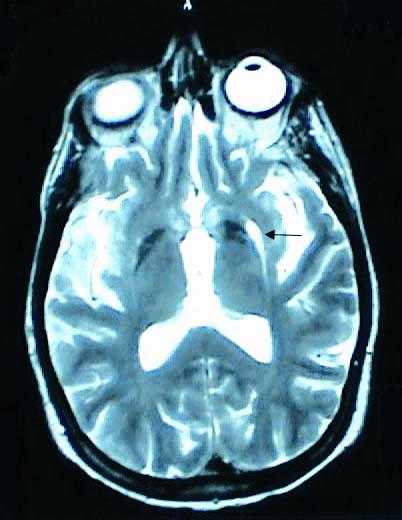

ภาพที่ 7. ภาพ MRI ของผู้ป่วย multiple system atrophy.

ผู้ป่วย MSA สามารถมีอาการร่วมอื่นๆ นอกเหนือจากอาการทางระบบประสาทอัตโนมัติพาร์กินโซนิซึม และอาการของสมองส่วนหลัง. อาการทาง pyramidal signs ดังเช่น brisk tendonreflexes, spasticity, extensor plantar responses และ pseudobulbar palsy มักพบได้บ่อย และสามารถตรวจพบได้ในช่วงแรกของผู้ป่วย MSA. อาการ dementia ถึงแม้ว่าจะพบน้อย และไม่เด่นชัด ถ้าเกิดขึ้นจะเป็นลักษณะอาการของ frontal lobe โดยส่วนใหญ่การวินิจฉัยโรค MSA จะอาศัยลักษณะอาการดังที่กล่าวไว้ข้างต้น ร่วมกับ diagnostic criteria ที่ได้กำหนดขึ้น.13 การตรวจทางห้องปฏิบัติการ โดยเฉพาะการตรวจ MRI จะช่วยบ่งบอกถึงรอยโรค และสนับสนุนลักษณะอาการที่เด่นในผู้ป่วยรายนั้นว่ามีพยาธิสภาพชัดเจนในสมองส่วนใด ดังเช่น MRI ในผู้ป่วย MSA-C มักปรากฏลักษณะของ brainstem and cerebellar atrophy. ลักษณะผิดปกติทาง MRI ที่พบได้มากกว่าร้อยละ 50 ของผู้ป่วย MSA โดยทั่วไป โดยเฉพาะในกลุ่ม MSA-P คือ hypointense signals on T2-weighted images เนื่องจากการสะสมของธาตุเหล็ก ร่วมกับ slit-like hyperintense signals on T2-weightd images ในส่วนของ putamen ส่วนนอก ลักษณะความผิดปกติของสมองส่วน Pons ซึ่งเกิดเนื่องจากการเสื่อมของ transversed pontine fibers และ midline raphe โดยที่ tegmentum ปกติ ทำให้ภาพของ MRI ในสมองส่วนนั้นมีลักษณะคล้าย Hot-cross bun (ภาพที่ 8)